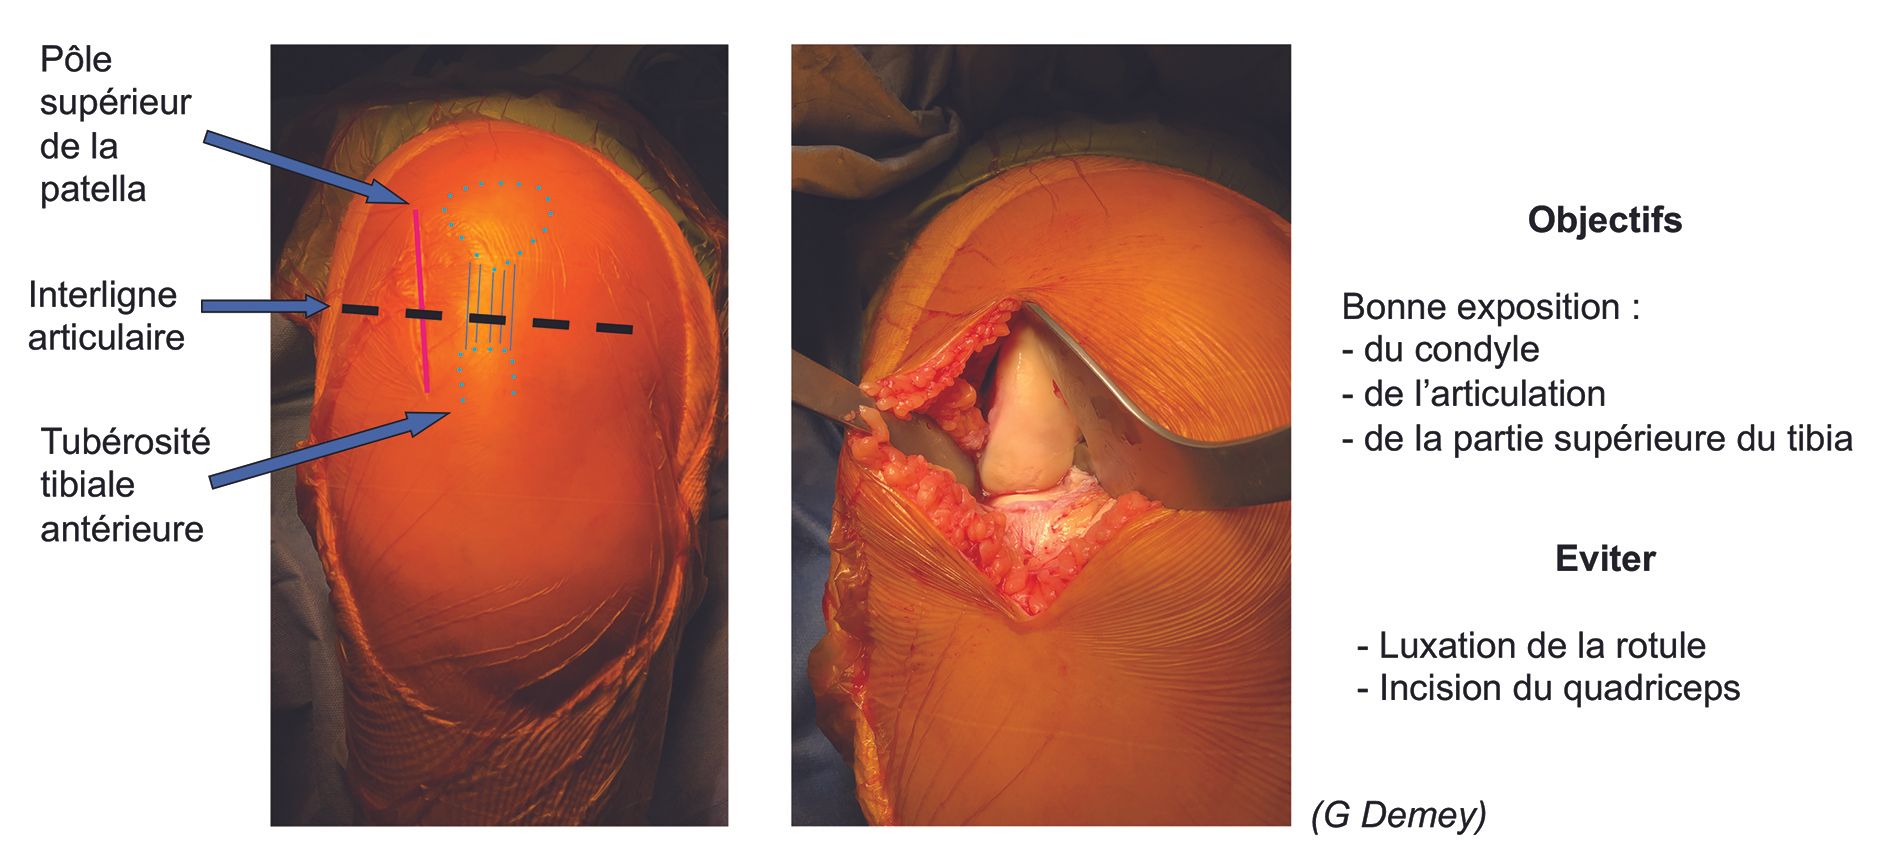

A lateral parapatellar portal is used with a skin incision of only 8–10cm, from the superior edge of patella to 2cm beneath the joint line (Figs 5 and 6). This limited ‘mini-invasive’ approach clearly exposes tibia and lateral condyle without the need for dislocation of the patella or a quadriceps incision, thus facilitating postoperative functional recovery.

The arthrotomy should be minimal to avoid damaging the trochlear cartilage, medial meniscus or cruciate ligaments (which will have been checked at the start of the procedure). It is important to leave sufficient tissue over the patellar side to be able to close the arthrotomy, by routinely retaining the Hoffa fat pad pediculated to the anterolateral meniscocapsular structures (Fig. 7). Osteophytes should be removed from the notch, but any osteophytes on the lateral condyle should be kept since they are commonly used to support the femoral head.

No ligament release

Any soft-tissue release from tibia should be kept to a minimum, with zero ligament release since it could cause overcorrection in the frontal plane.21 Care should also be taken not to damage the collateral ligaments with the retractors during the procedure.